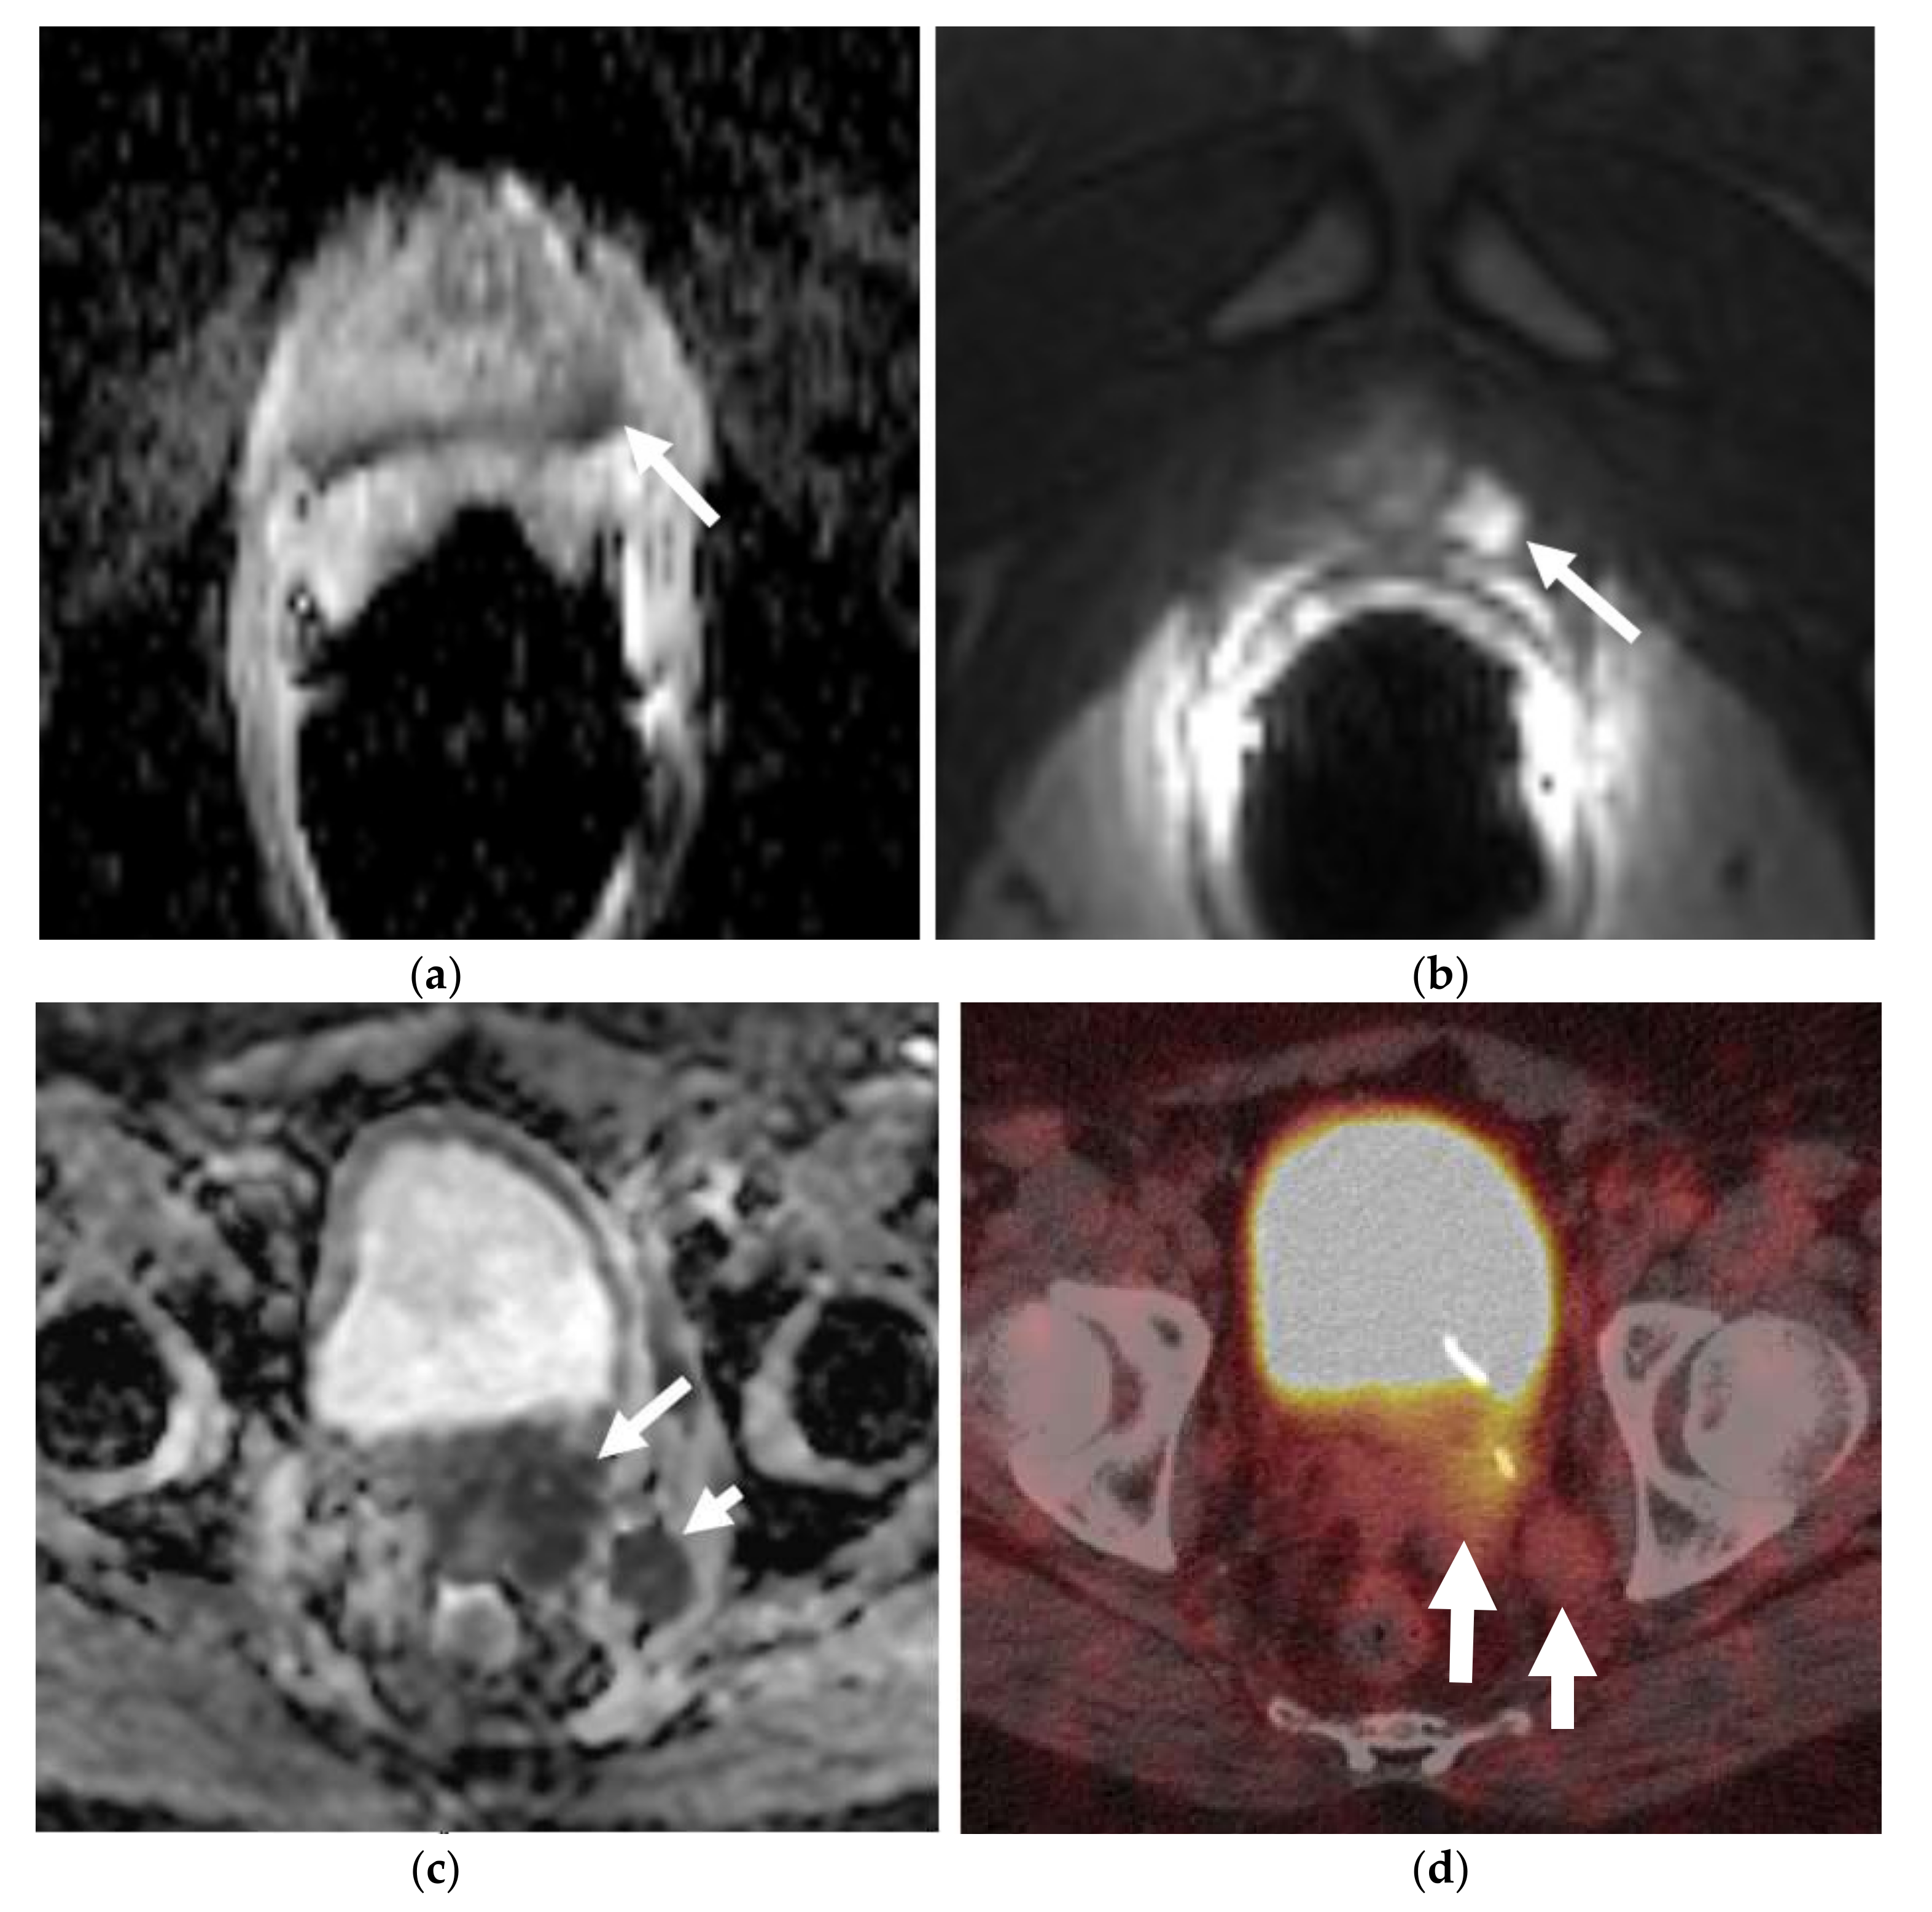

Figure 1.

A 60-year-old man with lower retroperitoneal lymphadenopathy on PET-CT, found during work-up for dermatomyositis and abnormal digital rectal exam. T2W (a) and ADC (b) MR images through the prostate show a hypointense mass (long arrow) with restricted diffusion in the left posterolateral peripheral zone of the prostatic apex. Large field of view axial T1W MR image (c) of the pelvis shows right external iliac lymphadenopathy (short arrow). This was biopsy-proven metastatic small cell carcinoma of the prostate.

Prostate cancer is the most common non-cutaneous cancer in men worldwide. The year 2020 estimates for prostate cancer are about 191,930 new cases in the United States and 1,414,259 worldwide and it is the second leading cause of cancer death in men, behind lung cancer [1,2]. Neuroendocrine prostate cancer (NEPC) represents an aggressive subtype of prostate cancer, accounting for 0.5–2% of all prostate cancers and typically has a high metastatic potential and poor prognosis [3]. It can arise de novo (Figure 1), but much more commonly occurs as a mechanism of treatment resistance during therapy for conventional prostatic adenocarcinoma, when they are also termed castration-resistant prostate cancers (CRPC) [4]. Thus, the incidence of NEPCs increases after hormonal therapy and these are thought to arise from lineage plasticity induced by androgen receptor-targeted therapy [5]. They represent a challenge in the radiological and pathological diagnosis, as well as in the clinical management of the patients with limited therapies and very poor prognosis. Our objective is to offer an overview of their radiological characteristics with radiopathologic correlations and illustrations.

Multiparametric MRI (mpMRI) is now considered to be the standard imaging evaluation of choice when suspecting prostate cancer. Members of PI-RADS (version 2.1) steering committee recommend using 3T MRI scanners over 1.5T machines for prostatic evaluation, as it increases the signal-to-noise ratio (SNR), leading to an increase in both temporal and spatial resolution. If only 1.5T scanners are available or in the case of inherently low SNR sequences, such as DWI, they recommend the use of endorectal coil (ERC) which has the ability to increase SNR at any magnetic field strength [32]. Most tumors appear isointense to normal prostate tissue on T1-weighted sequences which serve as a baseline for the contrast-enhanced MRI, delineate the prostate outline, and can also demonstrate post-biopsy hemorrhage and periprostatic fat invasion. T2-weighted (T2W) sequences are used to evaluate prostatic zonal anatomy, primarily evaluate the transitional zone or central gland tumors, asses for seminal vesicle or nodal involvement, and detect extra-prostatic extension (EPE). Peripheral zone cancers usually demonstrate ill-defined T2 hypointense focal lesions with restricted diffusion and are primarily evaluated on ADC/DWI images (Figure 1). Transitional zone tumors appear hypointense with spiculated, ill-defined margins and smudgy appearance on T2W images. These lesions may also invade the urethral sphincter and anterior fibromuscular stroma [33,34]. While mpMRI is now considered the technique of choice for initial and local (T) tumor staging, PET/CT and PET/MRI have shown a great value in distant extraprostatic (N and M) staging (Figure 2), restaging after biomedical relapse, and response assessment after androgen deprivation therapy (ADR) [35,36,37,38]. The sensitivity, specificity, positive predictive value, and negative predictive value of multiparametric MRI for detection of EPE (Figure 3), were 48.7%, 73.9%, 35.9%, and 82.8%, respectively [39,40].